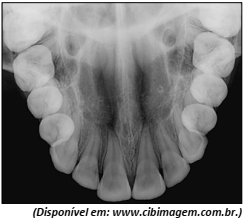

Observe a imagem.

Qual é o tipo de radiografia apresentada?

Oclusal.

Periapical.

Panorâmica.

Interproximal.

Telerradiografia.